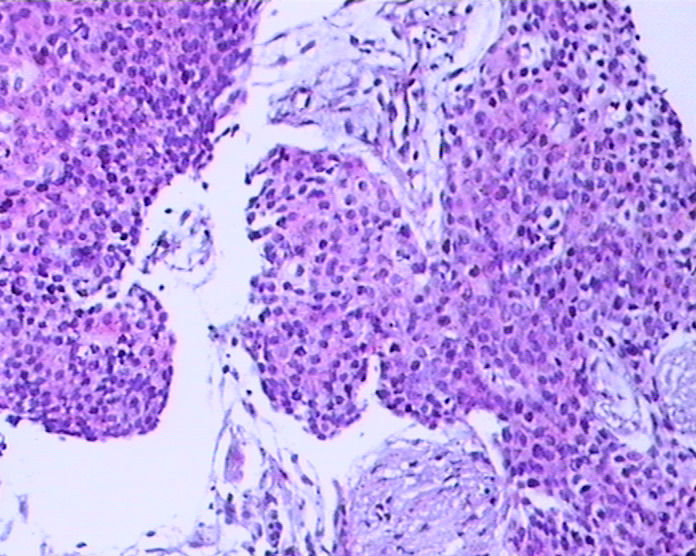

患者男性,51岁,发现右纵膈肿物,行穿刺活检。

参考诊断

鳞癌?

1。胸腺癌?

2.低分化鳞癌?

胸腺癌?